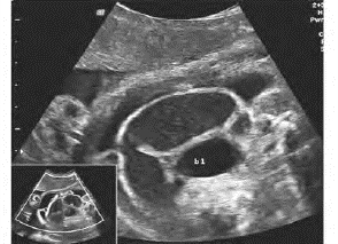

1.22第18章 胎儿超声心动图

1.22.3三、胎儿先天性心脏病